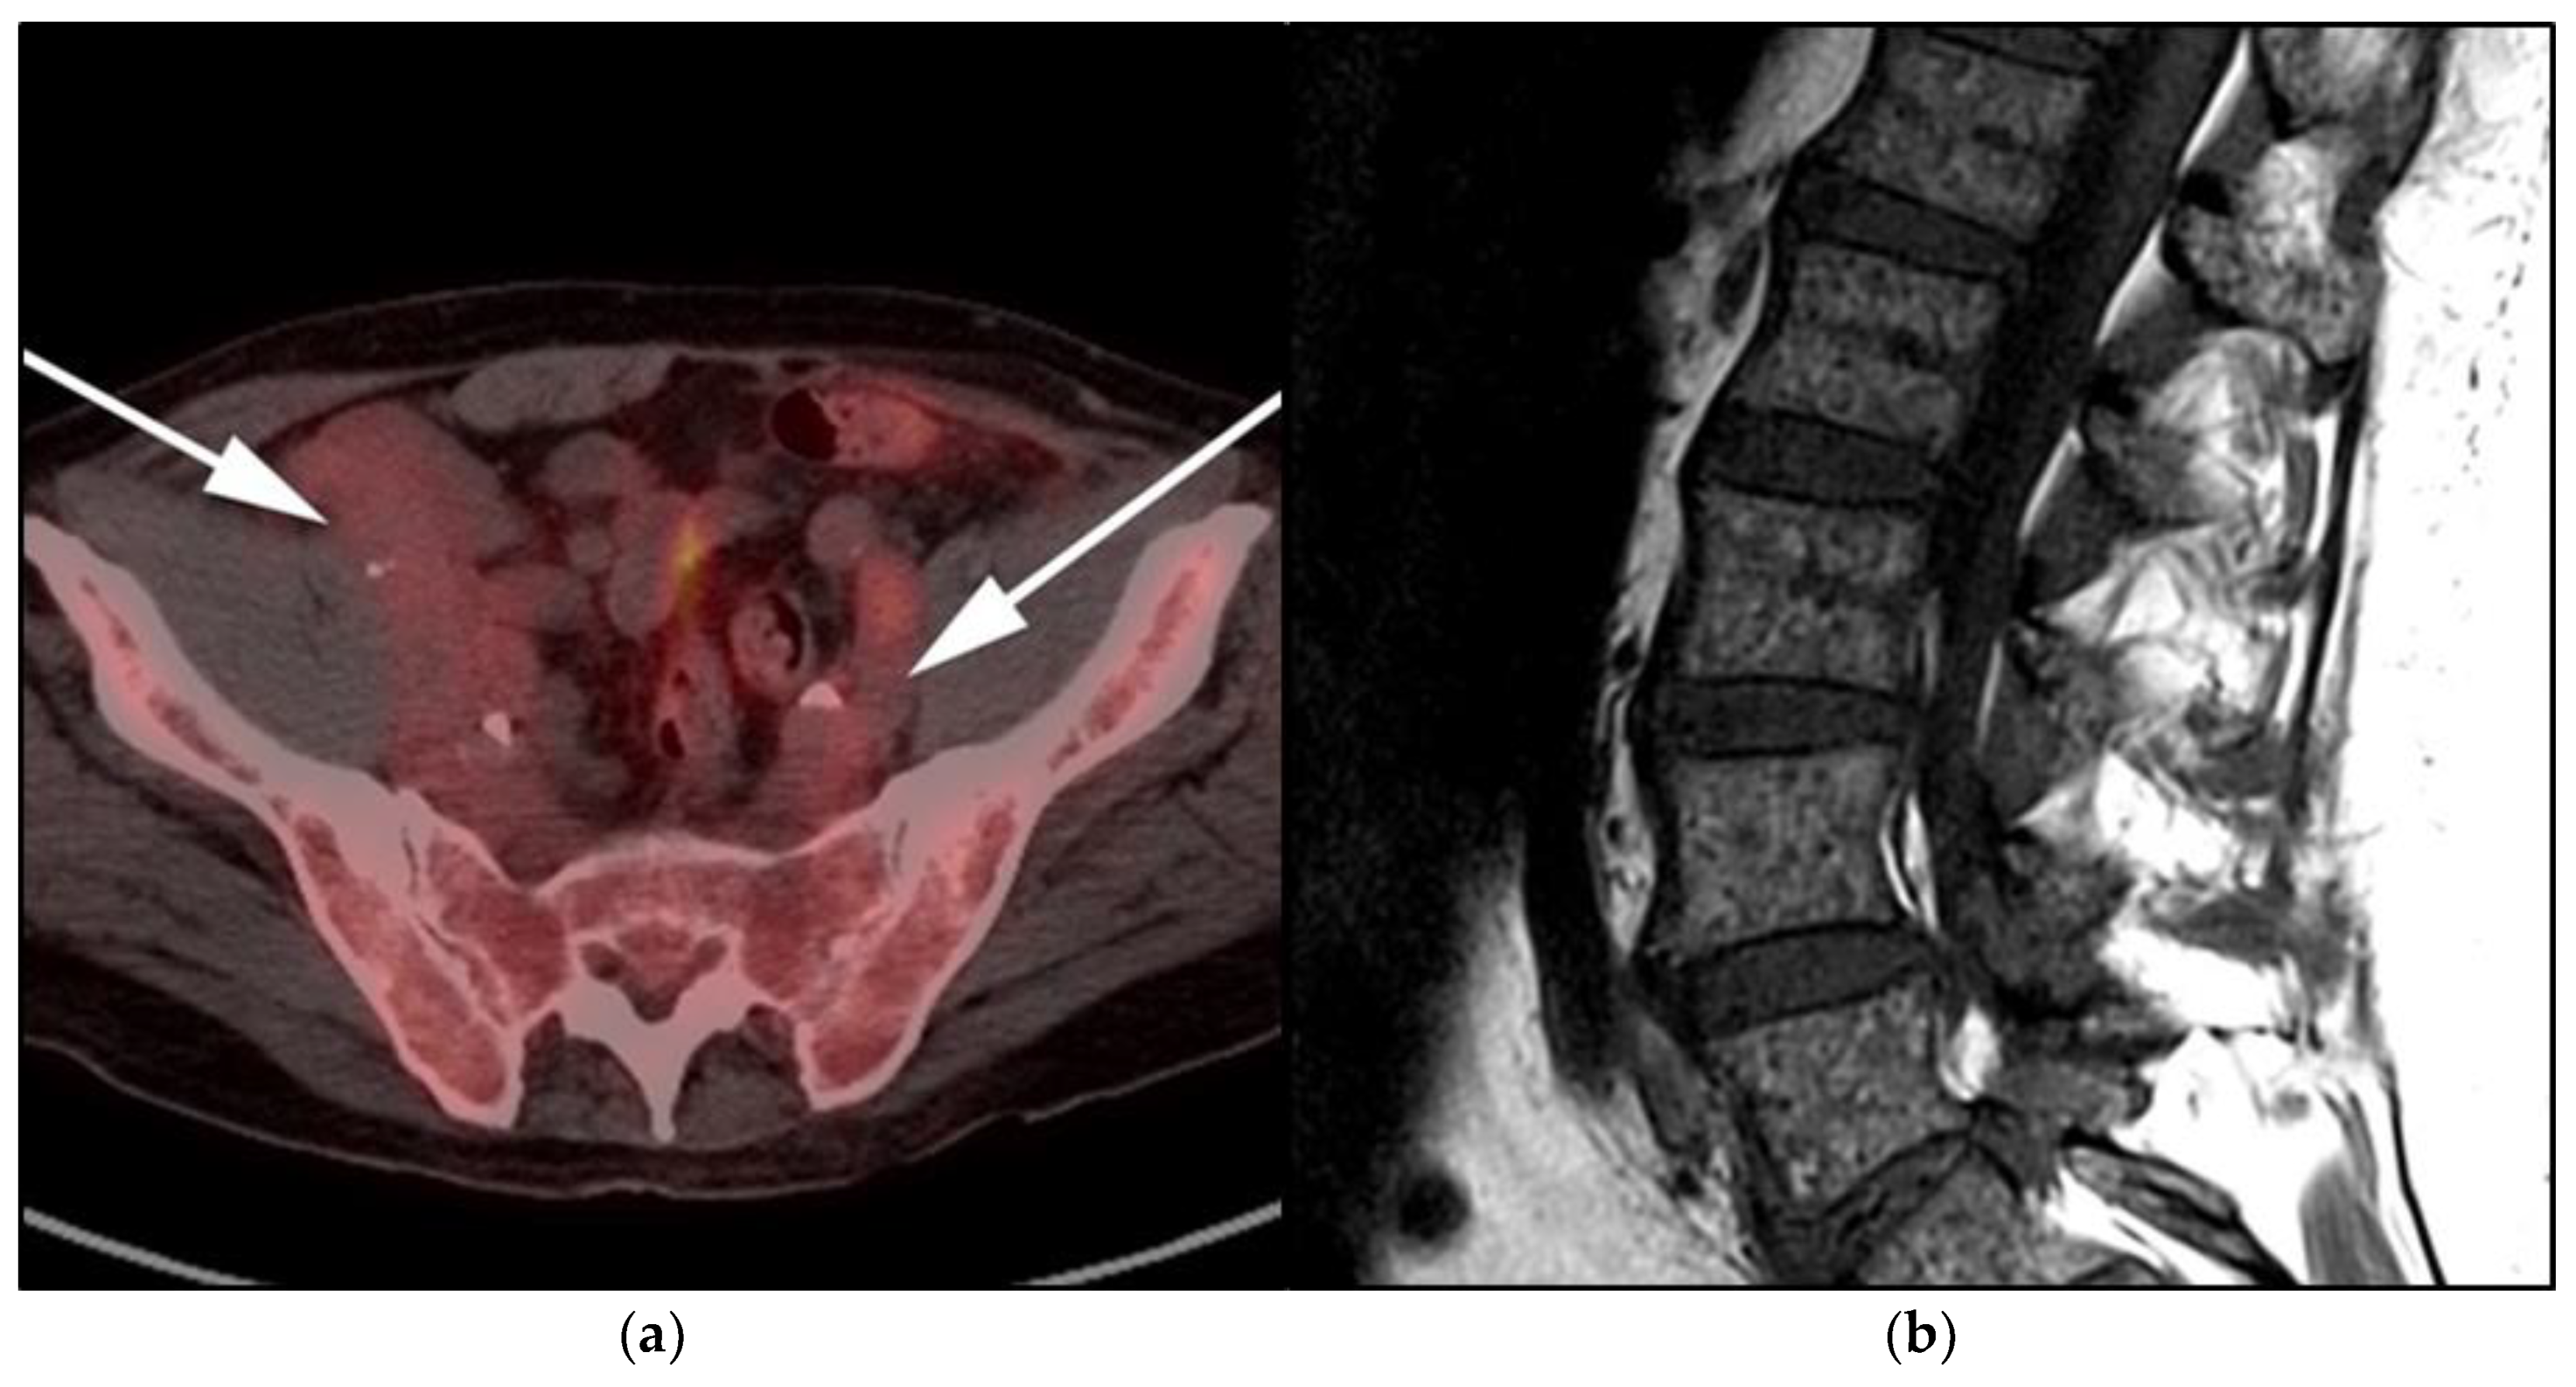

Figure 12.

Lymphoplasmacytic lymphoma. (a) Axial FDG PET/CT in the same patient as Figure 8 shows hypermetabolic adenopathy within the bilateral iliac chain (white arrows). (b) Sagittal MRI T1-weighted image in the same patient shows a diffuse variegated appearance of the marrow consistent with marrow infiltration as that seen in multiple myeloma but without definite focal lytic lesions. Lymphoplasmacytic lymphoma combines features of both malignant lymphoma and multiple myeloma.

Multimodality imaging, including CT, MRI, and/or 18F-FDG PET/CT, is essential for initial diagnosis, especially in extramedullary disease presentation. Imaging can be helpful in determining optimal biopsy sites, as well as the assessment of response to therapy and monitoring disease progression or transformation. Unlike MM, WM is not associated with definite osseous lytic lesions, a feature that can distinguish WM from MM. WM usually manifests as osteopenia, marrow space widening, and endosteal erosions [52,53] (Figure 11).

WM patients can also present with splenomegaly with or without focal lesions and lymphadenopathy typically within the axillary, retroperitoneal, and/or inguinal nodal stations (Figure 12). Cranial nerve deficits can be a manifestation of Bing–Neel syndrome, a rare CNS manifestation seen in WM disease [45,48,52,54]. In Bing–Neel syndrome, neurological symptoms can be directly related to infiltration by lymphoplasmacytic cells or indirectly result from the deposition of circulating IgM immunoglobulin on the brain parenchyma, spinal cord, or cranial or peripheral nerves (Figure 13). Additionally, 18F-FDG PET/CT plays an important role in monitoring therapeutic response after treatment initiation, especially with rituximab. WM patients tend to show elevated IgM levels, known as an IgM flare, which may mimic progressive disease. Imaging plays a pivotal role to differentiate between an IgM flare and true progression, thus obviating the need for repeated marrow biopsy [52]. Imaging may also help in excluding the development of myelodysplastic syndromes, acute leukemia, or DLBCL transformation [52].